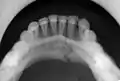

occlusal radiograph of a mandibular parasymphysis fracture